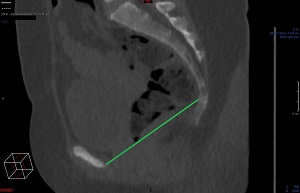

Tunna snitt-serien axialt i Power Viewern ("MPR"), snittjocklek 7-10 mm, skelettfönster. Scrolla fram till symfysens mitt. Mät det kortaste avståndet mellan symfysens kaudala-dorsala omfång och coccyx första böjbara led.